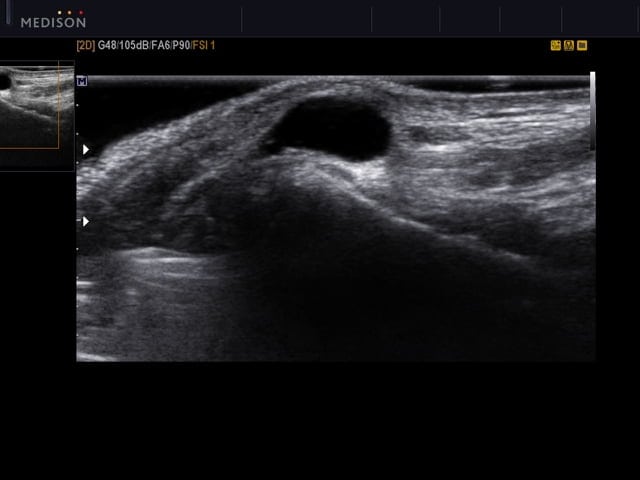

- ультразвуковое исследование визуализирует уплотнение. Оно позволяет установить наличие в стенке кисты кровеносных сосудов, что необходимо перед хирургическим вмешательством.